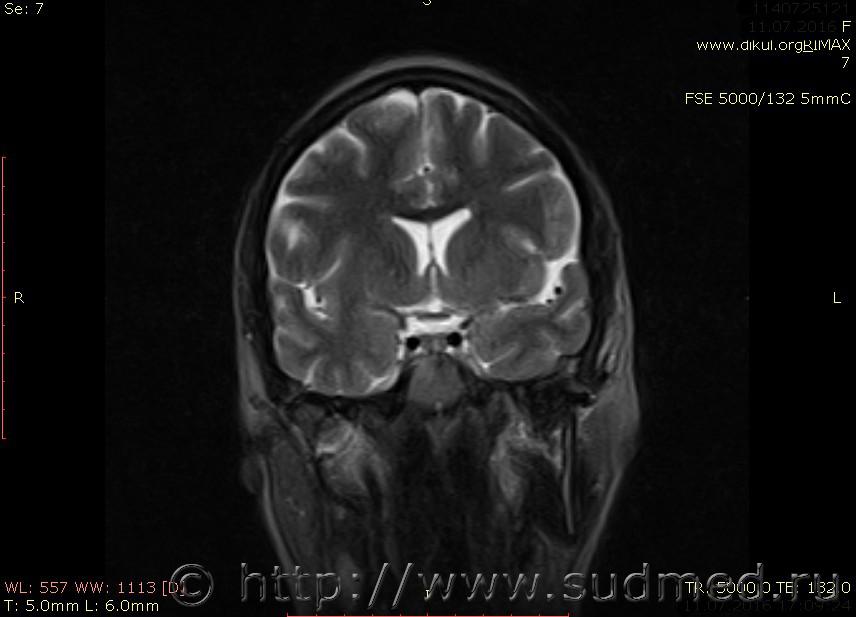

МРТ головного мозга показало: МР-данных за наличие очаговых изменений в веществе головного мозга на момент исследования не выявлено. МР-признаки нарушения соотношения в атланто-осевом суставе. Определяется ассиметрия положения зубовидного отростка С2 относительно боковых масс С1(справа 6,5; слева 4 мм.)

Сама по себе эта информация даёт основания подозревать вывих первого шейного позвонка, но однозначно не свидетельствует о наличии вывиха. Нужно смотреть на снимках наличие реакции со стороны мягких тканей, в т.ч. связочного аппарата, нужно анализировать особенности неврологической патологии, её динамику и проч.

Запрошен электронный вариант снимков из учреждения, где делалось МРТ. Т.к. с самого снимка делать копии не получается,очень мелкие кадры. Завтра попробую вставить в сообщение. (Но СМЭ снимок не смотрел, смотрел только мед.карту, в которой находилось описание МРТ).

Посмотрите пожалуйста снимки, надеюсь на них видны позвонки С1,С2?

Прошу прощения, попробую снова прикрепить файлы. Данные учреждения и пациента убраны.